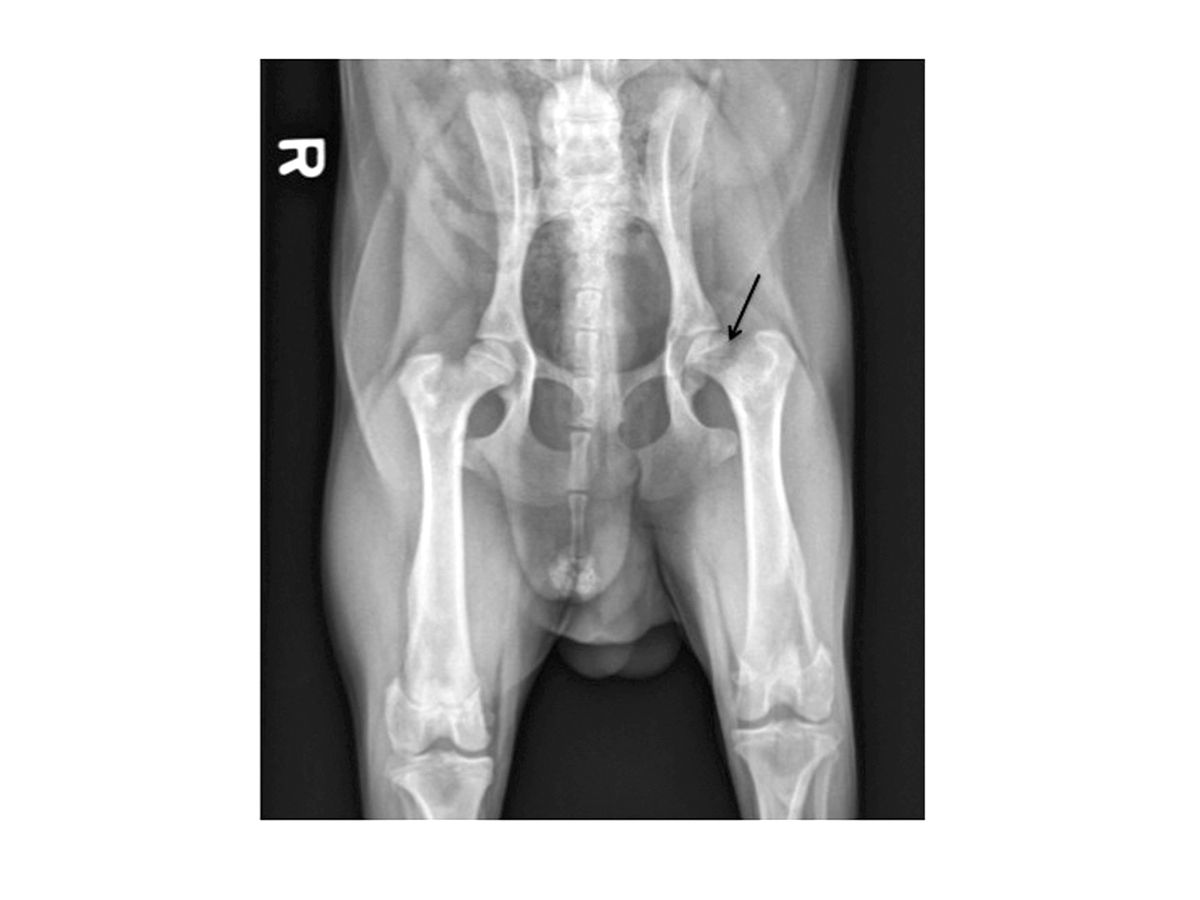

Radiographie postopératoire après une exérèse tête et col du fémur. La ligne d’ostéotomie part de la face médiale du grand trochanter et rejoint le petit trochanter pour limiter le contact interosseux.

Figure 5. Radiographie postopératoire après une exérèse tête et col du fémur. La ligne d’ostéotomie part de la face médiale du grand trochanter et rejoint le petit trochanter pour limiter le contact interosseux.© Darryl L. Millis

Pour obtenir d’excellents résultats avec l’ETCF, il est essentiel d’adopter une bonne technique opératoire. Un abord crâniolatéral de l’articulation coxofémorale est réalisé et la capsule articulaire est exposée. Une arthrotomie est effectuée en incisant la capsule articulaire juste au-dessus de son insertion sur le col du fémur. Le ligament rond est sectionné et la tête fémorale est luxée vers l’extérieur. Un instrument de type crochet à ovariectomie peut être utilisé pour surélever la tête fémorale par rapport à l’acétabulum et aider à protéger le nerf sciatique qui longe caudalement le col fémoral. Une petite scie électrique, une scie fil ou un ostéotome et un marteau peuvent être utilisés pour réaliser l’ostéotomie. Dans certains cas, l’os peut être très mou ou fracturé et une pince-gouge peut alors suffire à retirer le reste de la tête fémorale. Pour tenir compte de l’antéversion de la tête et du col, il faut appliquer une rotation externe suffisante au fémur, en amenant par exemple la pointe du tarse (tuber calcis) contre la paroi thoracique latérale. L’ostéotomie est effectuée de la base du grand trochanter jusqu’au petit trochanter (Figure 3). Après ETCF, il est nécessaire de palper le site d’ostéotomie pour détecter tout éclat d’os restant, généralement sur la face caudomédiale du fémur. Le cas échéant, les excroissances osseuses peuvent être retirées avec une pince gouge et le site d’ostéotomie peut ensuite être lissé à l’aide d’une râpe. Puis, la zone est abondamment rincée pour éliminer les fragments restants ou les poussières d’os. La néoarticulation est mobilisée pour s’assurer qu’il n’existe pas de contact interosseux important. La partie de la capsule articulaire venant du bord dorsal de l’acétabulum peut alors être suturée sur la face ventrale de l’acétabulum pour interposer une couche de tissu mou entre l’acétabulum et le fémur ostéotomisé (Figure 4). Des radiographies postopératoires doivent être réalisées pour confirmer que la totalité de la tête et du col a bien été retirée (Figure 5).